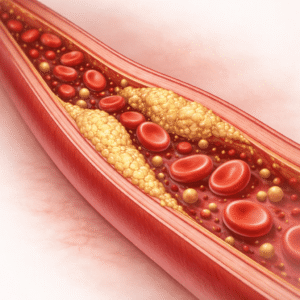

Kolesterolin hallinta

Mitkä ovat kolesterolin hallinta? Kolesteroli on veressä oleva rasvan kaltainen…